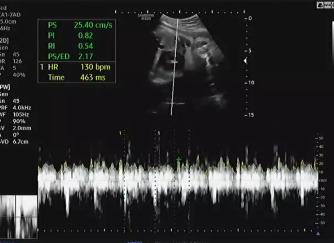

임신 37주가 되어 병원에 내원했다. 초음파를 보는데 아기는 건강하게 잘 있다고 열심히 태동을 하며 인사를 건네 왔다. 머리둘레(BPD), 허벅지 둘레(FL), 복부둘레(AC)를 측정하고 태아가 어느 정도로 성장하였는지 확인했다. 다행히 아기의 머리둘레가 주수보다 작게 나와서 자연 분만하기 좋을 것이라고 이야기를 했다.